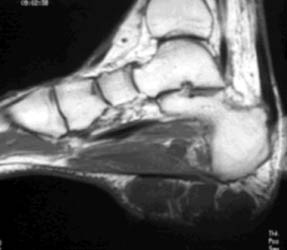

A rare low-grade soft tissue sarcoma that occurs at a mean age of 50 years. It often presents as a slowly growing painful and tender soft-tissue mass, usually affecting the extremities. 40 to 45 percent are metastatic lesions at the time of presentation. On CT or plain radiography, a soft tissue mass with ring, arc, stippled, and highly opaque calcifications may be noted. They most commonly are isointense to muscle on T1 and hyperintense (isointense to fat) on T2 W images. T1W post Gd images show contrast enhancement. Low signal intensity foci of calcification are present. They may mimic a cyst or myxoma.

64-year-old male with a painless soft tissue mass in the lateral aspect of the right heel. Plain radiograph demonstrates a densely calcified mass in this region. MR demonstrates this mass to be isointense on T1 and hyperintense on T2W images, with a central area of hypointense calcification.